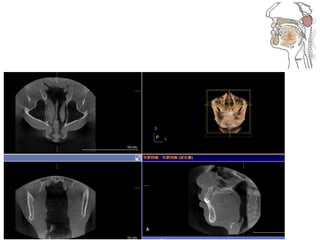

RME

• Maxillary constriction in particular has been

postulated to play a role in the pathophysiology

of OSA because of its association with low tongue

posture that may contribute to the orophayrnx

airway narrowing (Subtelny 1954).

• Pirelli et al. grouped 31 children with OSA and

followed them up to 4 months after RME

treatment. All of these children had their apnea-

hypoapnea index decreased while their mean

maxillary cross sectional width expanded to

about 4.5mm.